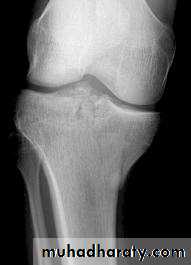

Tibial plateau fractures:Direct blow or fall from height may cause fracture of one tibial condyle or both.

Fracture lateral condyle is the commonest named as bumper fracture

caused by a force that abducts the tibia upon femur while the foot is fixed on ground.Patient usually is an adult, the knee joint is swollen, bruises, there is diffuse tenderness and doughy feel of haemarthrosis.

ligaments injuries must be excluded.

Imaging : X-ray

: anteroposterior, lateral & oblique views.

CT -Scan may used to detect amount of depression and comminuation.Tibial plateau fracture